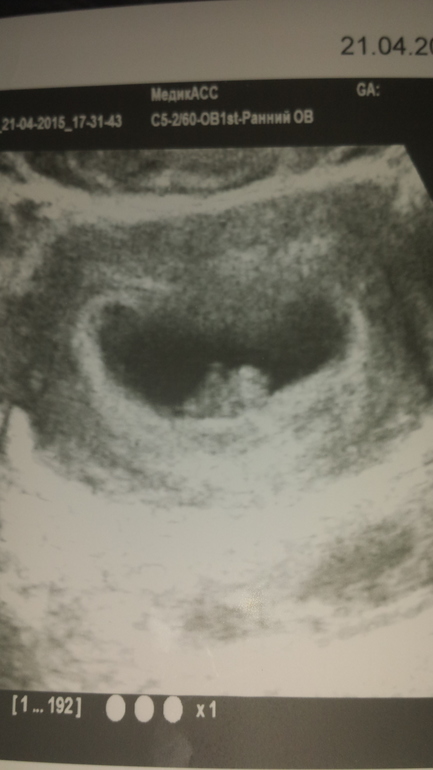

Вот как было видно у меня в 6н и 2д) эмбриончик 5мм и визуализировалось сердцебиение)руки и ноги точно уже позже)9308d65b232253a21d52bb4a00e45536.jpg

Ну вон видно же головастика)))) голова и туловище)))

Видно-видно,там желточный мешочек еще!мой радовался когда эту фоточку показала))